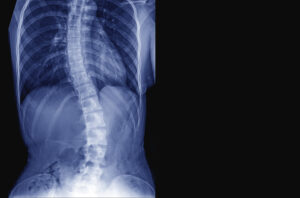

側弯症 Scoliosis

背骨が左右に10度以上捻じれた状態を側弯症と呼びます。そのうち約8割が原因不明な「突発性側弯症」で特に10歳以降の思春期の女子に起こりやすい病気です。他に不良姿勢が原因の機能的側弯症や、生まれつき背骨に捻じれを生じる構築性側弯症、遺伝子異常(骨の過剰成長が特徴のマルファン症候群)による側弯症、加齢や生活習慣による変性側弯症などがあります。

背骨の捻じれが大きくなると肩や腰の高さに左右差が出てきたり、腰や背中の痛み、心肺機能の低下を招く事もあります。